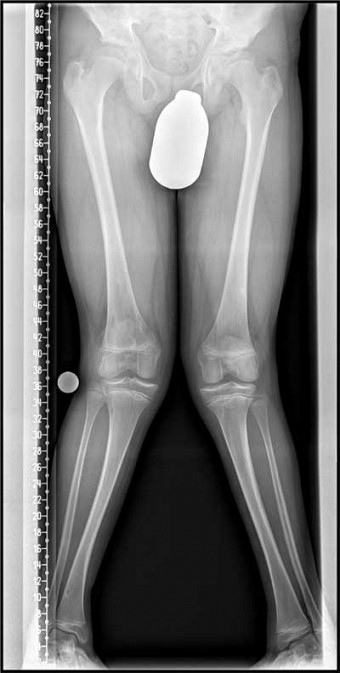

An erster Stelle steht die klinische Untersuchung durch den erfahrenen Kinderorthopäden. Dies ist bei allen Achsfehlstellungen und besonders bei Drehfehlstellungen für die Diagnose und Festlegung der weiteren Untersuchungsschritte entscheidend. Ausschlaggebend in der weiteren Diagnostik ist die korrekte Messung der knöchernen Beinachsen. Diese Messung kann nur mittels einer Röntgenaufnahme (Ganzbeinstandaufnahme) erfolgen. Gleichzeitig muss das Knochenalter durch eine Röntgenaufnahme der Hand bestimmt werden.

Das Ziel ist es, das weitere Wachstum zur Korrektur der Beinachsenfehlstellung zu nutzen. Durch gezieltes Verhindern von Wachstum an den z.B. kniegelenksnahen Wachstumsfugen am Ober- und Unterschenkel kann eine Achsenkorrektur im Sinne einer Begradigung der Beine erreicht werden.

Korrektur X- Beine durch

Wachstumslenkung. Hierbei wird die Wachstumsfuge auf der Innenseite des Kniegelenkes durch eine

kleine Platte am Wachstum gehemmt, sodass bei normal wachsender Außenseite eine Ausgradung des

Beines erfolgt